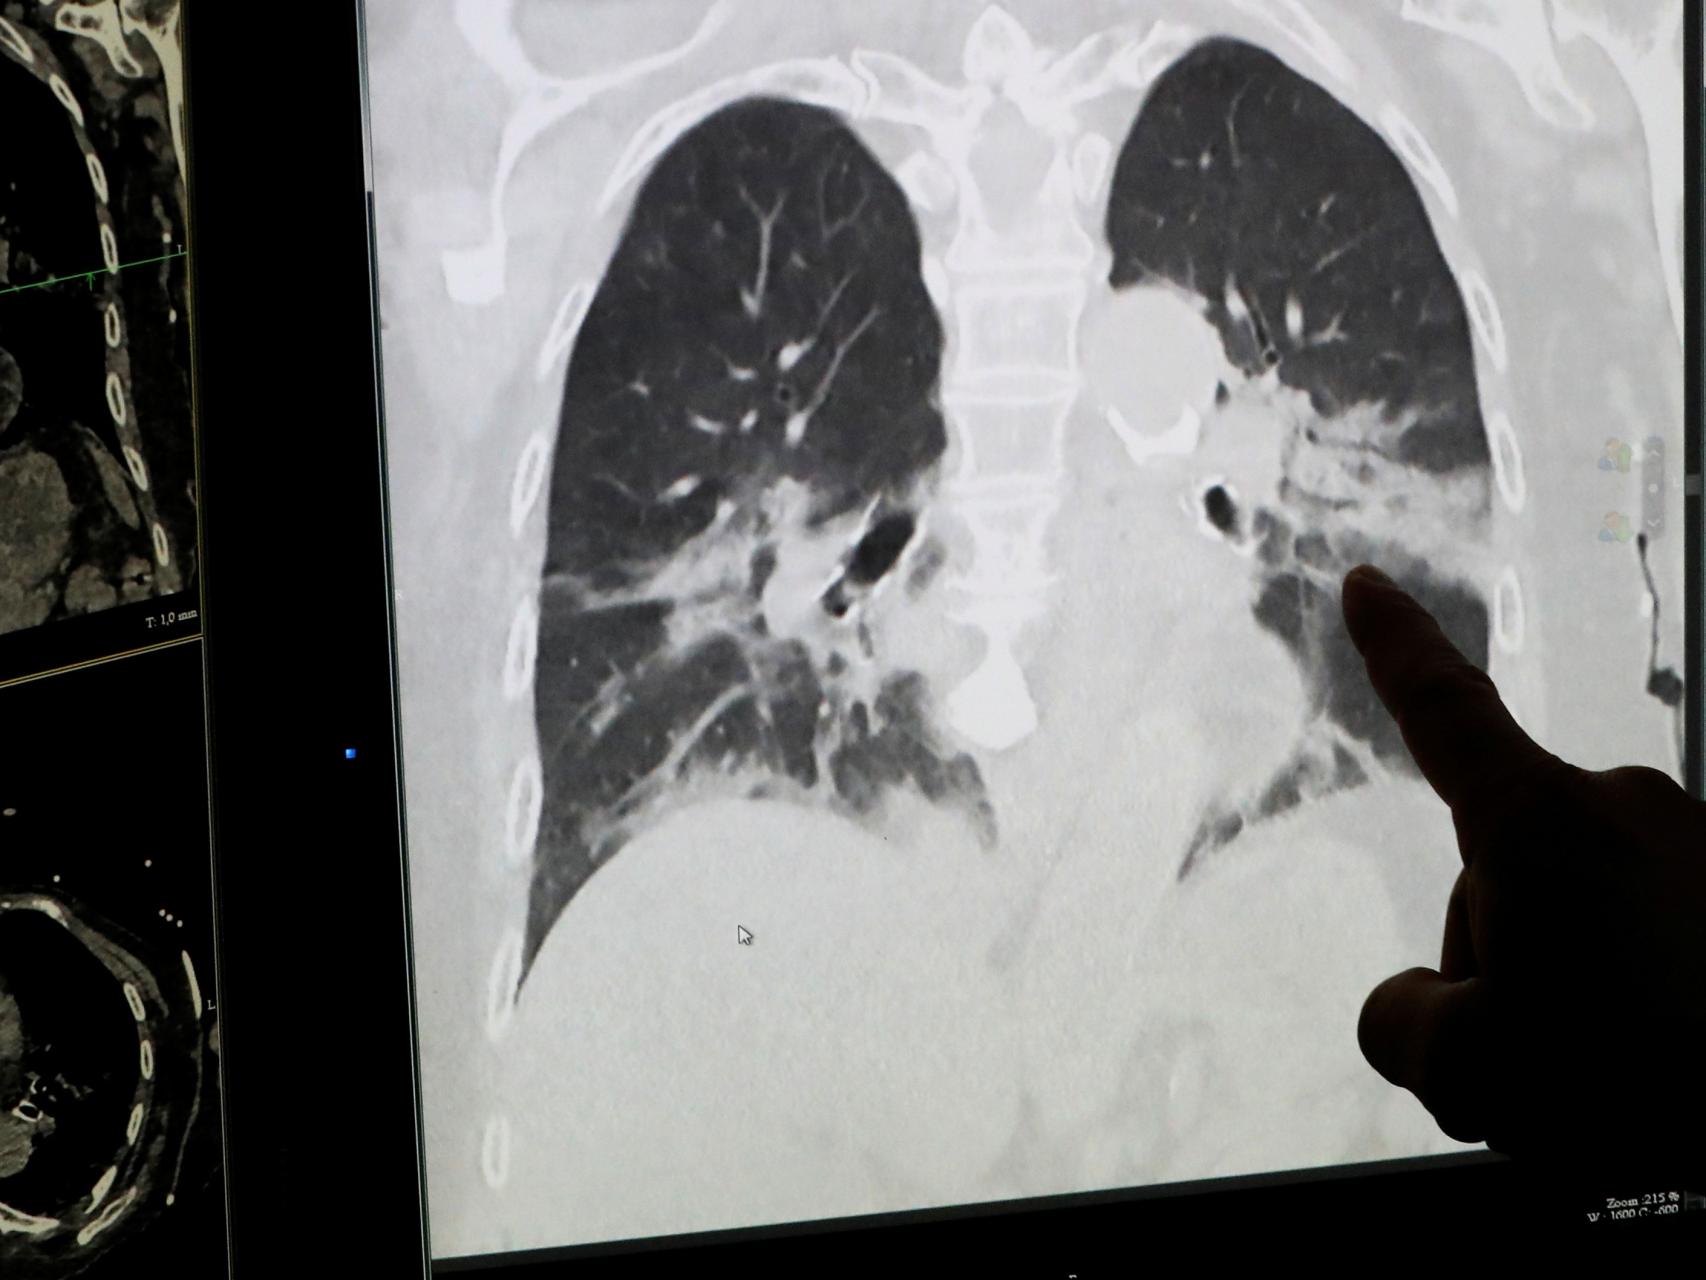

Un radiólogo muestra unos pulmones infectados por Covid-19.